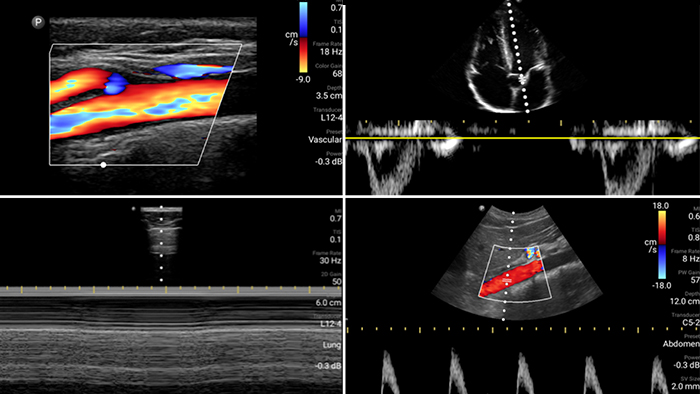

Broadband linear array transducer

Lumify L12-4 broadband linear array transducer

• 12 to 4 MHz extended operating frequency range

• Aperture size: 34mm

• 2D, steerable color Doppler, M-mode, advancedXRES and multivariate harmonic imaging, SonoCT

• High resolution imaging for shallow applications: soft tissue, vascular, superficial, musculoskeletal and lung

• Center line marker

• USB-C transducer with replaceable cable